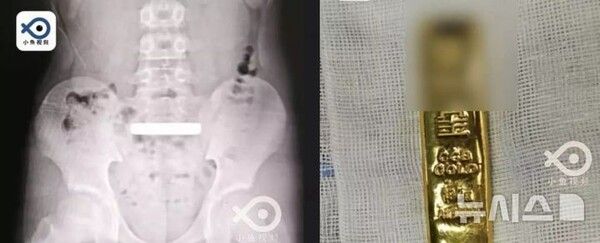

중국의 한 소년이 실수로 100g짜리 골드바를 삼키는 사고가 발생했다.

뉴시스 보도에 따르면, 12일(현지시각) 중국 온라인 매체 바스틸레포스트(bastille post)에 따르면, 장쑤성 쑤저우시에 사는 11살 샤오첸(가명)이 집에서 놀던 중 실수로 100g짜리 금괴를 삼켰다.

이후 시간이 갈수록 복통과 복부 팽만감이 심해졌고, 이를 알게 된 부모는 샤오첸을 쑤저우대학 부속 소아병원 응급실로 데려갔다.

엑스레이 촬영 결과 샤오첸의 위장에서 직사각형 모양의 밀도 높은 금속 물체를 발견했다.

아이의 설명을 듣고 골드바라고 추정한 의료진은 샤오첸을 일반외과에 입원시키고, 약물 치료를 통해 배변으로 골드바가 자연스럽게 배출되기를 기다렸다.

그러나 이틀이 지나도록 골드바는 배출되지 않았고 위치도 그대로였다.

의료진은 골드바의 크기가 커 장폐색이나 장 천공 위험을 우려했다. 결국 샤오첸의 나이를 고려해 개복 수술 대신 내시경을 이용해 골드바를 제거하기로 했다.

수술을 맡은 주진웨이와 저우샤오강 의사는 30분 만에 골드바를 꺼내는 데 성공했다. 꺼낸 골드바는 100g짜리였다. 현재 시세로 따지면 약 1500만원에 달했다.

샤오첸은 빠르게 회복해 이틀 후 정상적으로 식사하며 퇴원했다.